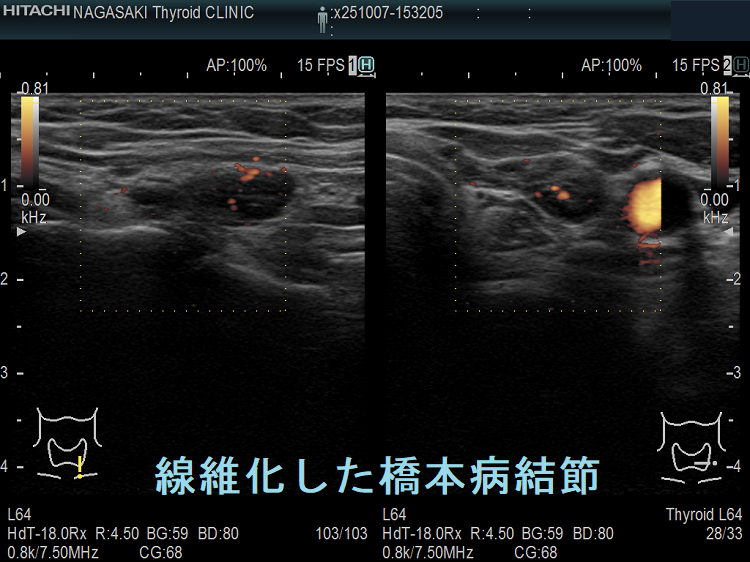

橋本病(慢性甲状腺炎)ではリンパ球浸潤に伴う炎症から濾胞細胞の好酸性変性[好酸性細胞(Hürthle細胞,ハーテル細胞)]・過形成、浮腫、線維化で結節性病変を形成[結節性橋本病(橋本病結節)]。病理学的に腺腫様甲状腺腫・腺腫様結節と同じで、橋本病(慢性甲状腺炎)を基盤とする腺腫様甲状腺腫・腺腫様結節。超音波(エコー)検査では内部が極めて低エコーのため甲状腺癌、甲状腺原発悪性リンパ腫と鑑別必要。細胞診では好酸性細胞、リンパ球集簇、炎症性多核巨細胞を認め、甲状腺乳頭癌ワルチン腫瘍型、通常型甲状腺乳頭癌・亜急性甲状腺炎と鑑別要。

橋本病(慢性甲状腺炎)では、リンパ球浸潤に伴う炎症から、濾胞細胞の好酸性変性・過形成、浮腫、線維化などの変化で結節性病変が形成されます[結節性橋本病(橋本病結節)]。病理学的には腺腫様甲状腺腫・腺腫様結節と同じ事で、橋本病(慢性甲状腺炎)を基盤とする腺腫様甲状腺腫・腺腫様結節になります。